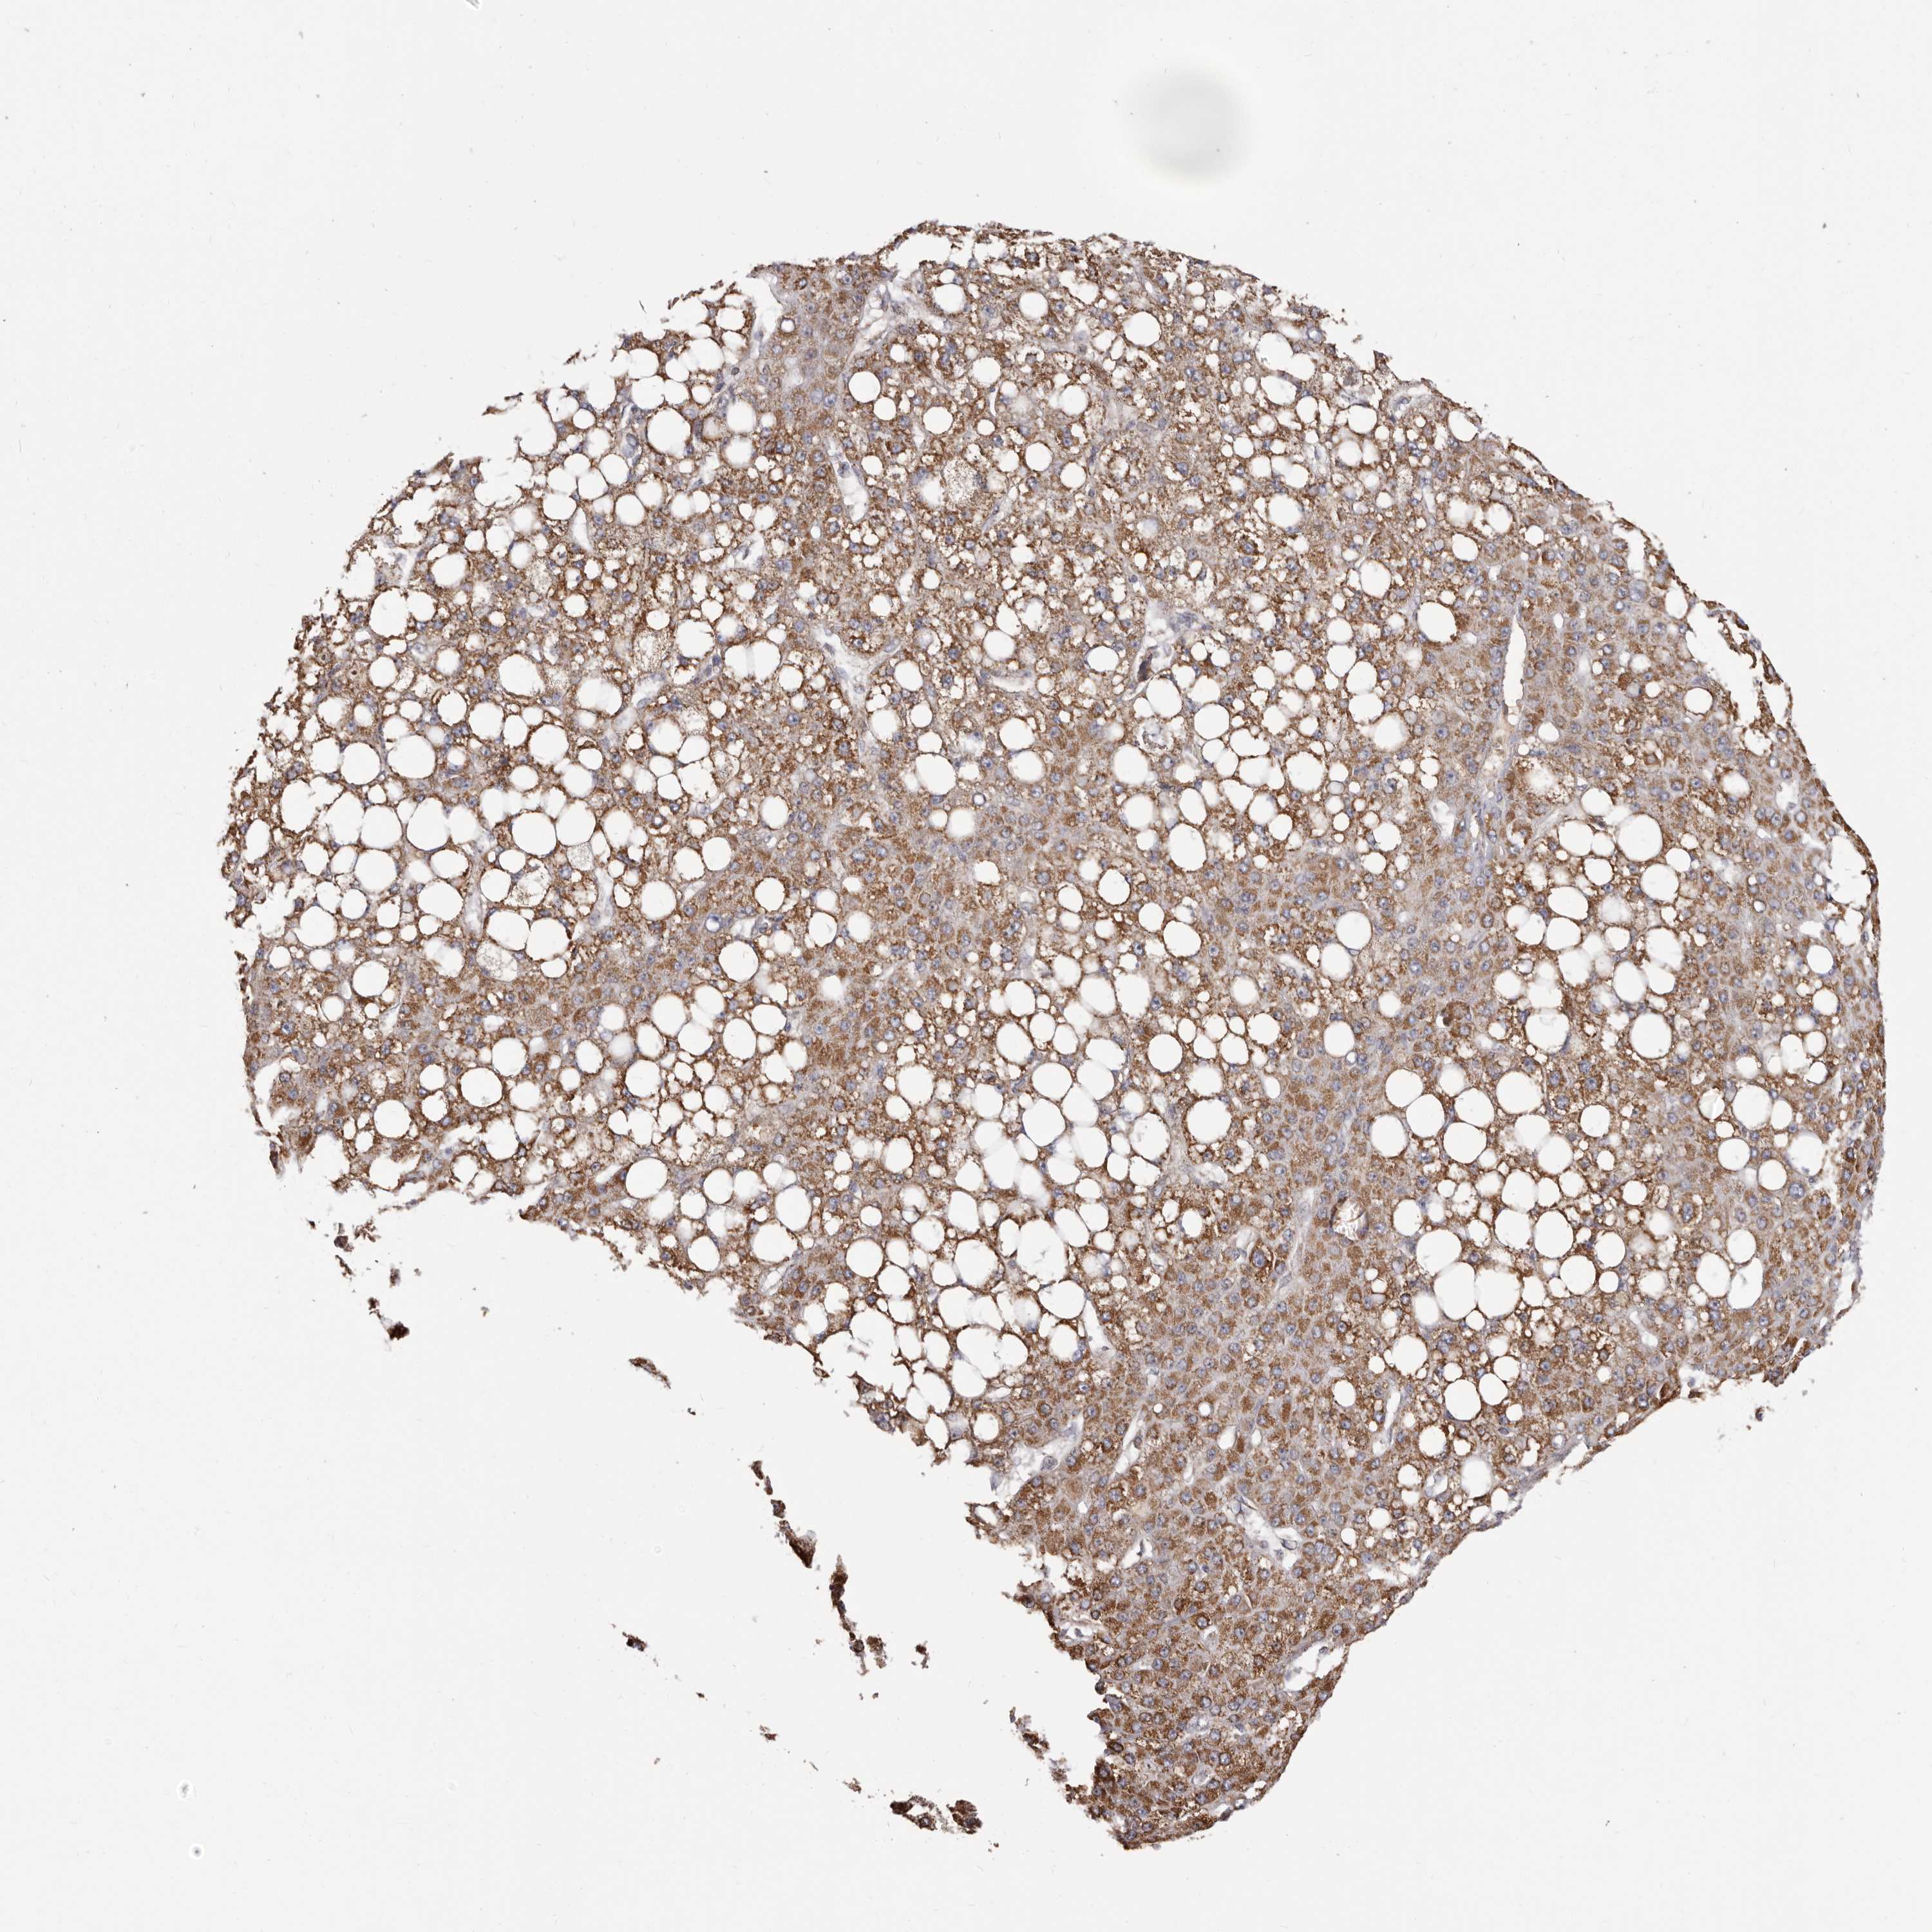

LIVER CANCER - Protein expressioni

A mouse-over function shows sample information and annotation data. Click on an image to view it in a full screen mode. Samples can be filtered based on level of antibody staining by selecting one or several of the following categories: high, medium, low and not detected. The assay and annotation is described here.

Note that samples used for immunohistochemistry by the Human Protein Atlas do not correspond to samples in the TCGA dataset.

Antibody stainingi

Antibody staining in the annotated cell types in the current human tissue is reported as not detected, low, medium, or high, based on conventional immunohistochemistry profiling in selected tissues. This score is based on the combination of the staining intensity and fraction of stained cells.

Each image is clickable and will lead to virtual microscopy that enables deeper exploration of all samples and also displays staining intensity scores, fraction scores and subcellular localization as well as patient and tissue information for each sample.

Antibody HPA029795

Antibody CAB022338

Staining

High

Medium

Low

Not detected

Intensity

Strong

Moderate

Weak

Negative

Quantity

>75%

75%-25%

<25%

None

Location

Nuclear

Cytoplasmic/membranous

Cytoplasmic/membranous,nuclear

Cholangiocarcinoma

Carcinoma, Hepatocellular, NOS